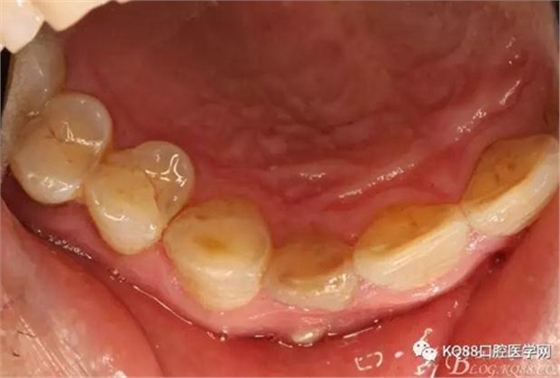

圖3.腭側(cè)觀;11腭側(cè)牙齦正常,21腭側(cè)樹(shù)脂充填完好